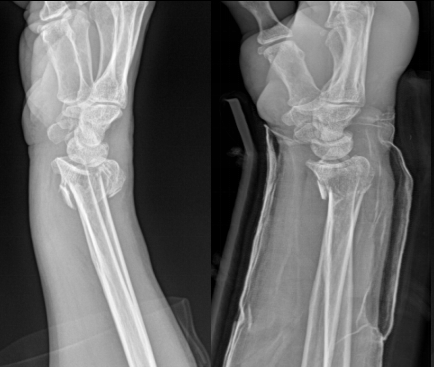

湖北日报客户端讯(通讯员周雪婷)近日,68岁的龙先生行走绊倒后右腕剧痛、活动受限,就医至枣阳市中医医院骨伤科。经X线检查,其确诊为“右侧尺桡骨骨折(桡骨远端粉碎性骨折伴骨片分离)”,随即收住入院。